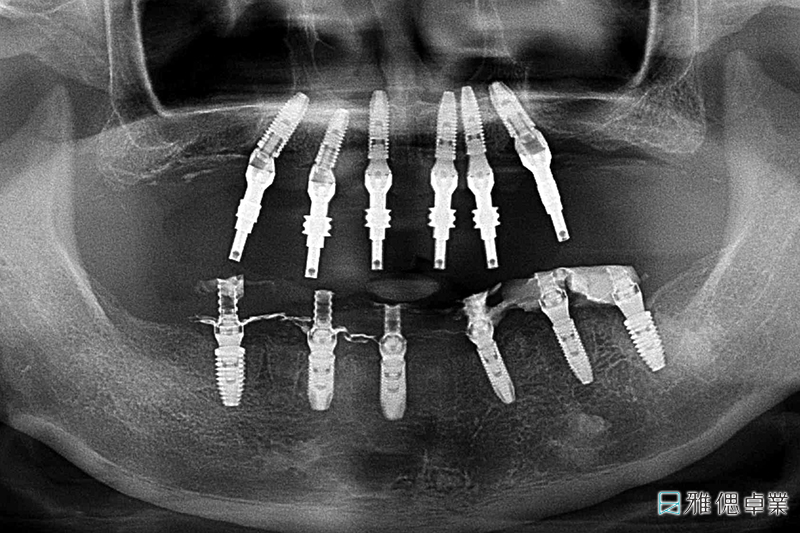

術前環口X光片,上顎只剩下2顆牙齒,下顎也有牙周、排列、咬合等問題

治療過程中的環口X光片